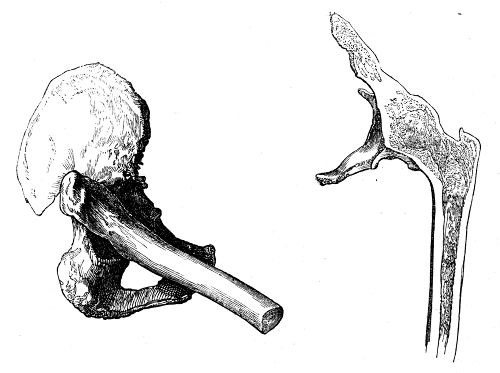

| Coxalgia | 81 |

| Alterations of Form in the Head of the Femur | 86 |